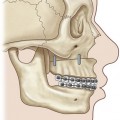

When the extremity is amputated or ischemic and the delay to surgery or anticipated length of time for debridement and definitive skeletal stabilization exceeds 6 hours, provisional revascularization can be done with use of a shunt, such as a Javid, Ishihara, or comparable segment of plastic tubing (Fig. 12.2). While different shunts are available, their use is similar. Whichever shunt is chosen (primarily by what might be available for use by the vascular surgeons), it is generally flushed with heparinized saline and then clamped. The concentration of this is usually 100 units heparin per cc saline. The shunt is then carefully slipped into the ends of the vessels to be shunted (artery to artery). The shunt is either held in place with moist umbilical tapes placed around the vessels and clamped tight with a piece of red rubber catheter (Fig. 12.2), or some shunts come with a special clamp which goes around the artery and holds it flush on the shunt. While generally utilized for only short periods of time (i.e., minutes to a few hours), these types of shunt have recently been utilized to great effect in the conflict in the Middle East for up to 8 hours on major arteries, without systemic heparinization. In this application, however, their use should only be necessary for the time it will take to perform an initial debridement and bony fixation. Another option is rapidly to perform reversed vein grafting between the arterial ends to re-establish arterial inflow. After definitive skeletal stabilization, the length of the vein graft can be adjusted and the anastomosis revised.